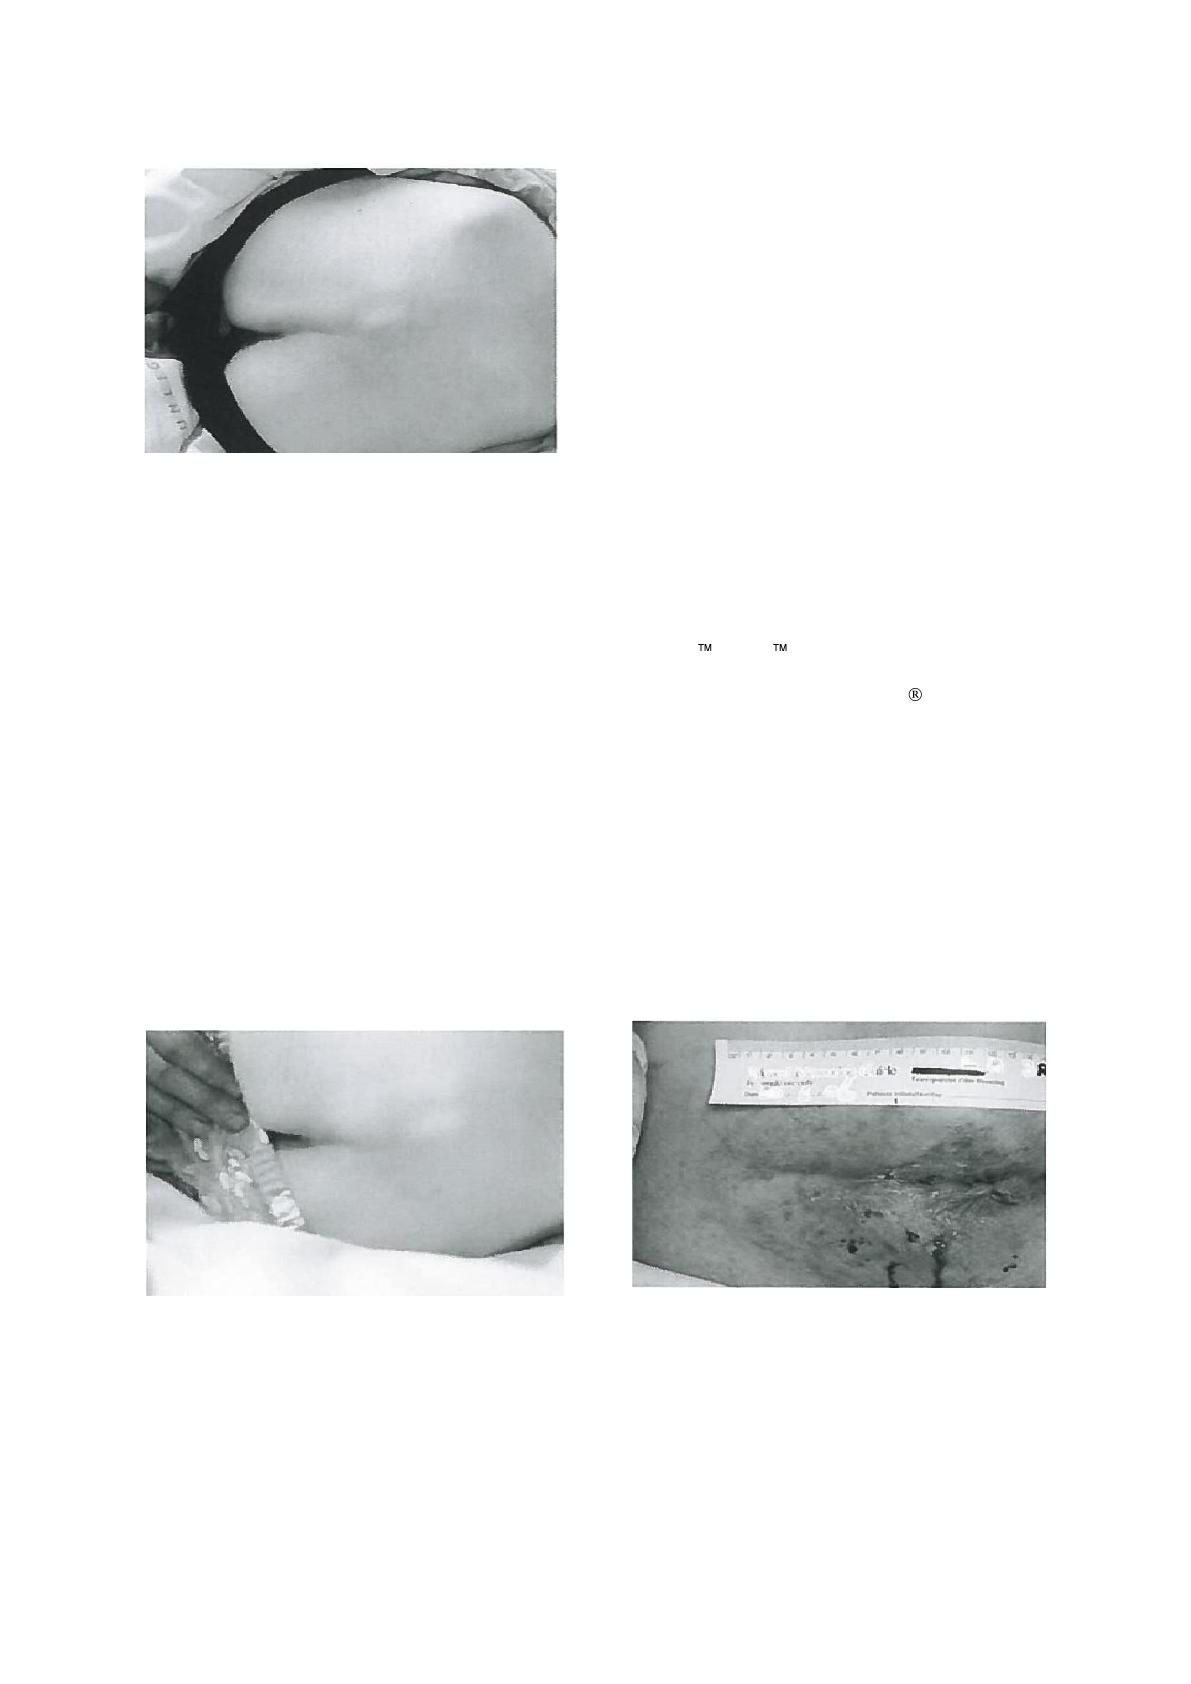

La pression est une force de charge verticale, comme les

fesses appuyant sur le matelas ou le siège. Le cisaillement

est une force de charge tangentielle ou parallèle par

exemple quand le patient descend en glissant peu à peu

vers l’extrémité du lit, mais sa peau colle au drap ou au

matelas ce qui étire alors et distend les tissus en contact

immédiats (Bliss, 1993). La friction décrit deux surfaces

en contact se déplaçant en sens contraire comme

lorsque le patient descend vers le bas du lit en glissant

sans que la peau ne colle à la surface du drap, ou, les

frottements qui se produisent entre une partie du corps

et une autre, par exemple le talon descendant la crête

tibiale. Plusieurs facteurs intrinsèques contribuent aussi à

un risque accru d’escarres (Encadré 1).